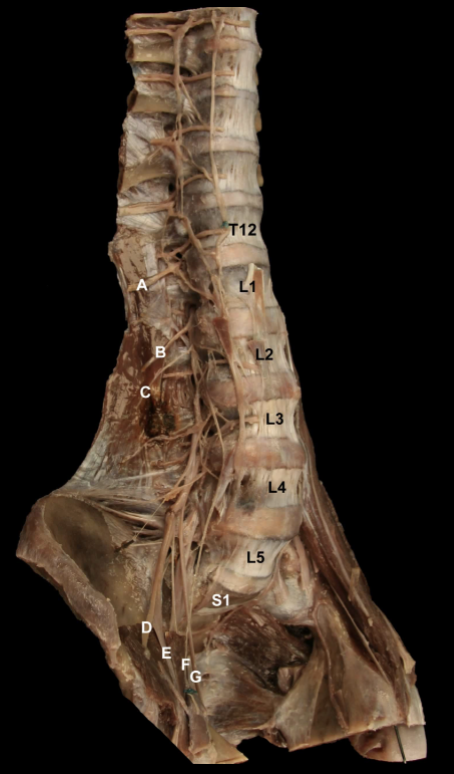

<p>Try and Identify the nerves and nerve roots of he <strong>Lumbarsacral Plexus&nbsp;</strong></p>

Try and Identify the nerves and nerve roots of he Lumbarsacral Plexus

A: Iliohypogastric n (L1)

B: Ilioinguinal n. (L1)

C: Lateral Cutaneous n. of the Thigh (L2-L3)

D: Femoral n. (L1-L4).

E: Geniofemoral n. (L1-L2)

F: Obturator n. (L2-L4)

G: Lumbosacral trunk (L4-L5)

H: Sciatic n. (L4-S3)

I: Genitofemoral n. (L1-L2).